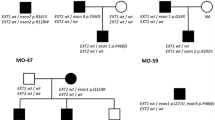

We found EXT1 and EXT2 heterozygous mutations in 28 out 33 (84.9 %) unrelated probands from our cohort. In total, we demonstrated 26 different mutational hits, since two of them were recurrent. Eighteen causative alterations (54.6 %) were identified in EXT1, while ten (30.3 %) were shown in EXT2. The remaining five cases (15.1 %) were negative for both EXT1 and EXT2 mutations. DNA sequencing has allowed for the detection of causative changes in 26 (78.8 %) probands, whereas MLPA showed intragenic copy number changes in two (6.1 %) further cases. Out of 28 molecularly confirmed unrelated probands, six cases (21.4 %) occurred due to de novo mutation while 22 (78.6 %) inherited the disease causing variant from an affected parent. According to HGMD® Professional 2013.4 and LOVD v.2.0 databases, out of 26 different mutations demonstrated in this study, 15 alterations were novel, whereas 11 were previously reported elsewhere (HGMD, Fokkema et al. 2011). Nine out of the 15 novel single nucleotide variants (SNVs) were identified in EXT1 and six in EXT2. For the description of the mutations and their reference to literature data, see Table 2. Out of 28 mutations detected by us, 23 (82.1 %) represented inactivating variants (17 frameshift, three nonsense, three splicing mutations). The remaining causative changes were two intragenic deletions (both in EXT2) and three missense substitutions (all in EXT1).

In all sporadic cases, presence of the mutation was excluded in both healthy parents, thus confirming their de novo occurrence in the probands. In familial cases, the identified alterations were checked for co-segregation with the phenotype and were not shown in the unaffected family members. Furthermore, all three missense variants were predicted to be probably damaging in most of the in silico analyses performed by us with the use of Mutation Taster 2, PolyPhen2, and SIFT software (Table 3).

In keeping with the past reports, EXT1 mutations are usually distributed throughout the entire protein sequence, while EXT2 lesions cluster in the first half of the protein (Jennes et al. 2009). However, in a large Italian cohort described by Ciavarella et al. (2013), 50.1 % of all EXT1 mutations were localized in exons 1 and 2. Our findings based on Polish patients support the hypothesis that there may be an excess of mutations in the first two exons of EXT1. In our cohort, mutation in exons 1 or 2 was identified in ten of 18 (55.6 %) EXT1 mutation carriers, which comprised 30.3 % of our initial cohort (ten probands out of 33). Therefore, we propose that diagnostic screening of HME Polish patients should start with the sequencing of the first two exons of EXT1, followed by sequencing of the rest of the gene. Next, in the case of negative results, we suggest EXT2 sequencing followed by copy number assays for EXT1/EXT2 exons.